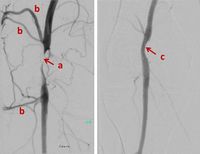

Interventional procedures using ionising radiation have revolutionised medicine in the past few decades for therapy and palliation, resulting in more patients being offered treatments that would not have been possible before with more invasive open surgery. The vast majority of interventional procedures are performed as “minimal invasive percutaneous therapies”.

Physicians, assisted by nurses and radiographers, perform X-ray guided interventions as an alternative to conventional surgery. Most of these interventions are less invasive, the recovery periods are shorter, and for many types of interventions the complication rate is lower. In addition, some patients who may not tolerate anaesthesia and conventional surgery, as well as lesions that were not previously accessible, can now be treated by less-invasive image-guided interventions. In addition, interventional procedures offer new therapies where options of other medical specialties do not exist, such as embolization of liver tumours with chemical drugs or radioisotopes (SIRT).

Interventions are usually guided by fluoroscopy. Radiographic cine series or stored images from fluoroscopy are taken to document the outcome of diagnosis or treatment. Interventions can also be guided by computed tomography (CT) imaging, with images taken while the interventionalist steps behind a shield or out of the room, or by CT fluoroscopy, in which the interventionalist stays at the patient for obtaining images during device manipulation.